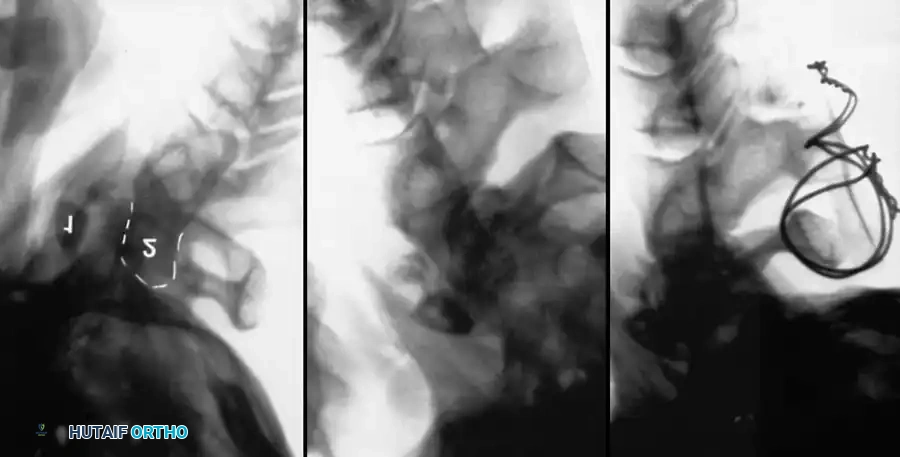

Posterior Cervical Fusion (PCF) and Instrumentation

Indications: Posterior tension band failure, irreducible facet dislocations requiring open reduction, or multi-level instability.

Surgical Steps:

1. Open Reduction: If a facet is dislocated, carefully lever the inferior articular process of the superior vertebra over the superior articular process of the inferior vertebra using a Penfield elevator.

2. Lateral Mass Screw Fixation:

* Utilize the Magerl or Roy-Camille trajectory.

* Magerl Technique: The entry point is 1 mm medial and 1 mm superior to the center of the lateral mass. The drill is angled 25 degrees laterally (to avoid the vertebral artery) and 15 degrees cephalad (to avoid the exiting nerve root).

3. Rod Contouring: Contour titanium or cobalt-chrome rods to match the patient's natural cervical lordosis and secure them to the screw heads with set screws.

4. Decortication and Fusion: Aggressively decorticate the lateral masses and facet joints with a high-speed burr. Pack the gutters with cancellous autograft (often harvested from the iliac crest) or high-quality allograft.

Fig 7. Posterior cervical lateral mass screw and rod construct, providing excellent biomechanical stability for posterior tension band failures.